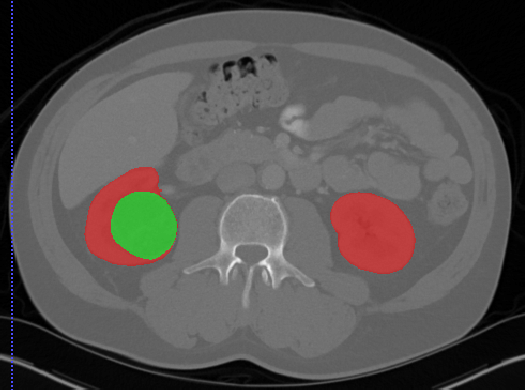

Kits19

| 名称 | 标注内容 | 类型 | 模态 | 数量 | 标签格式 | 文件格式 |

|---|---|---|---|---|---|---|

| Kits19 | 肾肿瘤 | 分割 |